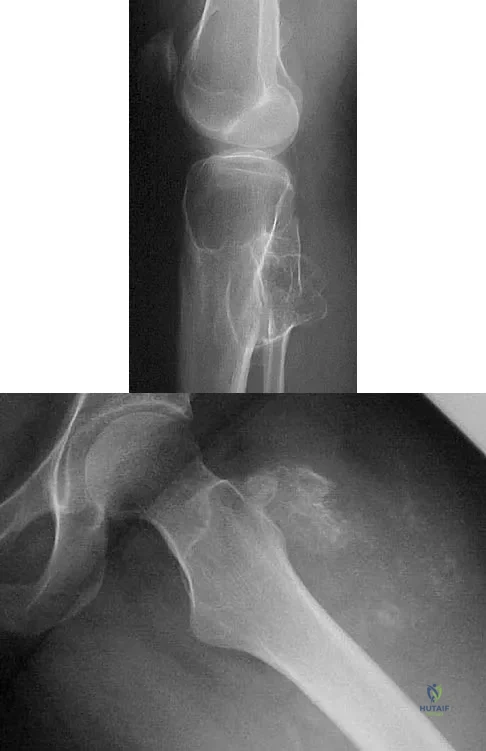

A 23-year-old man has had right posterolateral knee pain and occasional lateral calf dysesthesias for the past 8 months. A radiograph, CT scan, MRI scans, and a biopsy specimen are shown in Figures 62a through 62e. What is the most likely diagnosis?

Explanation